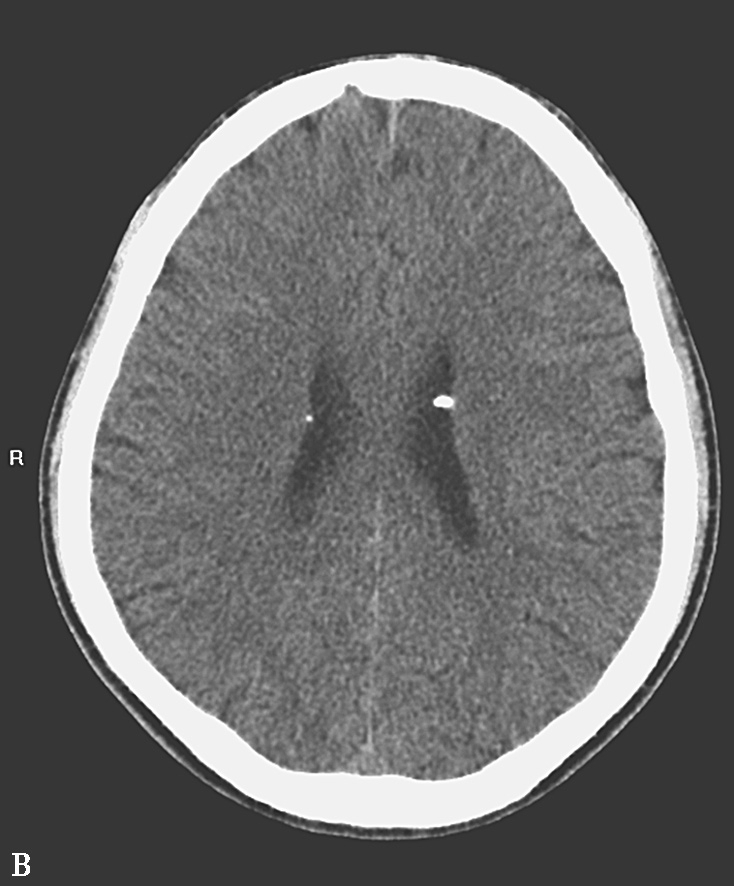

图1-6 结节性硬化

A、B.CT平扫,示双侧侧脑室室管膜下可见多发钙化结节,部分突入脑室内